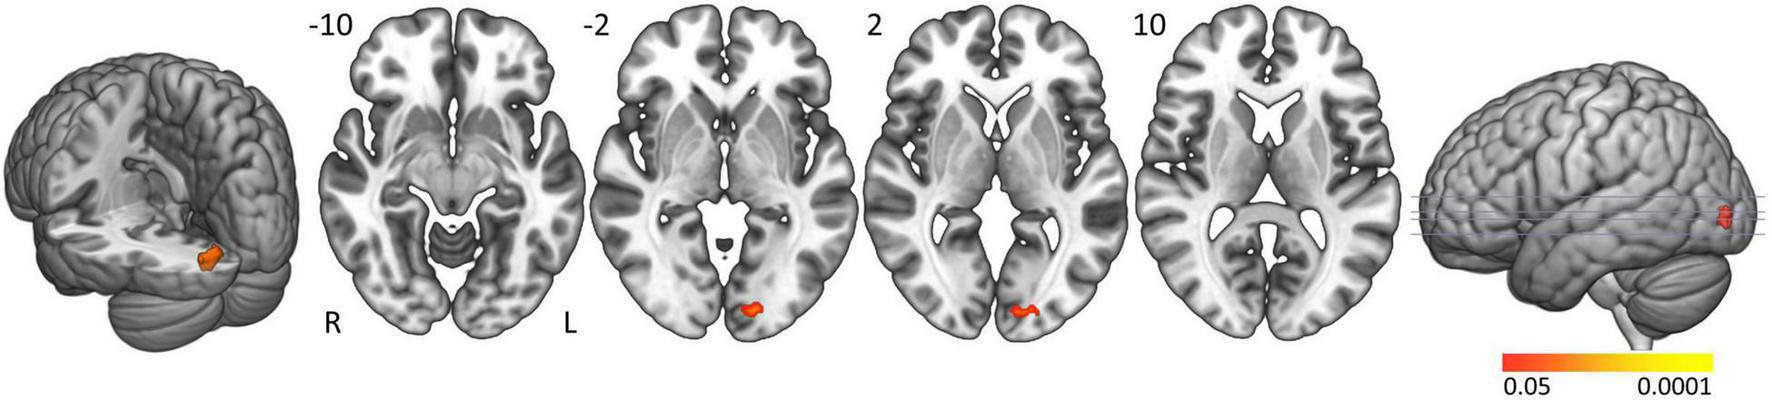

In controls the activation clusters in general were smaller compared to people with narcolepsy type 1 and no significant activation was seen in the brainstem. Formal comparison between groups elicited significantly greater activation in people with narcolepsy type 1 in the left calcarine and lingual gyri (Brodmann area 17; cluster size: 43 voxels; peak z-value: 3.88; cluster-corrected p-value = 0.0463; Z-max MNI coordinates: −42, −4, 36) when actively resisting sleep (Figure 2). No clusters were found with significantly more activation in controls compared to patients. Neither of the post hoc analyses with ESS scores and EDS duration as covariates of interest revealed significant correlations between these clinical markers and the observed group difference in the left calcarine and lingual gyri.

FIGURE 2

Active sleep resistance group differences. Axial slices displaying significant activation clusters that were significantly more activated in people with narcolepsy type 1 than in controls during active sleep resistance. Analyses were cluster-corrected (p < 0.05), masked for gray matter, and a minimum cluster size > 20 voxels was used.